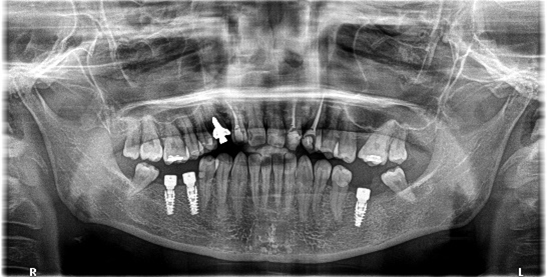

レントゲンで詳しく診てみると、虫歯が歯根のほうまで進行し、保存することができないことがわかり、抜歯しました。抜歯後、骨が大きく欠損していましたので、骨造成を行いインプラントを2本埋入しました。

抜歯後の欠損したところを補う方法には、部分入れ歯、ブリッジ、インプラントがあることを説明したところ、自分の歯と同じような感覚で嚙むことができるインプラントを選択されました。この方は、2016年に右下にインプラント治療をし、インプラントの良さを十分に理解しておられましたので、今回も2本歯を失ったところにインプラント治療を希望されました。今回もX-Guideを使った埋入で、安心安全に行うことできました。

Before

After